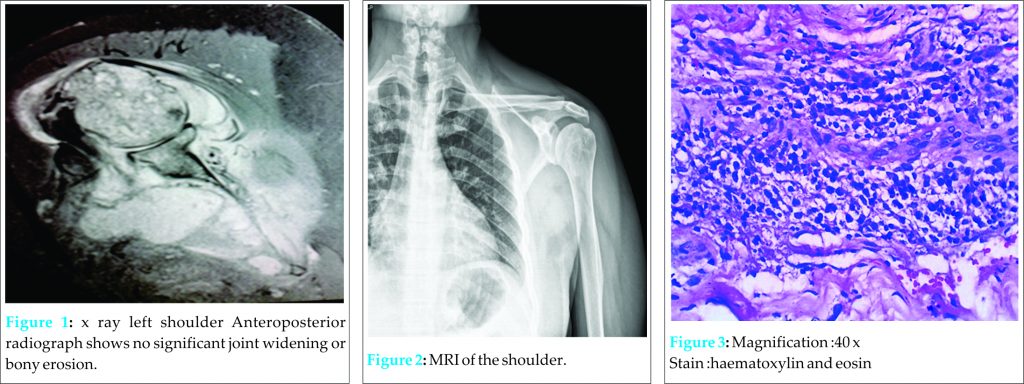

A 43-year-old man presented to the orthopaedic outpatient clinic with 2 months history of pain and limited range of motion in his left shoulder. His pain was insidious in onset, mild to moderate in intensity, aggravated by activities and associated with moderate rest and night pain. There was no history of direct or indirect trauma to the left shoulder. Patient was diagnosed as frozen shoulder at an outside facility and had been given intraarticular Depomedrol 40 mg injection for the same 40 days ago with no improvement in his symptoms. He had no fever, chills or rigors. He had no weight loss or loss of appetite. He is diabetic and has liver cirrhosis and is on treatment. On physical examination, the patient was afebrile, B.P was 110/70 mmHg, pulse rate-72beats/min. The skin colour and temperature of the left shoulder were normal, but the shoulder was tender to touch over the anterior joint line. Shoulder was very stiff and all shoulder movements were severely restricted. MRI was obtained [Fig 2] which showed extraosseous soft tissue enhancements around left shoulder with soft tissue abscess in inter muscular planes of supraspinatous, infraspinatous, subscapularis. glenoid joint effusion with distension of axillary recess.

Blood test revealed normal white cell count with normal differential count, CRP-13.4 mg/l (normal<5.0 mg/l). The erythrocyte sedimentation rate was raised, at 88 mm/hour (normal range,0-20 mm/hour ) Aspiration of shoulder joint was performed and fluid was sent for aerobic and anaerobic culture, AFB staining, Mycobacterium culture, and Mycobacterium genetic testing. Aerobic cultures identified methicillin –resistant Staphylococcus aureus. Arthroscopic lavage of the joint was done and articular fluid sent for repeat aerobic and anaerobic culture. Synovial biopsy was obtained and sent for histopathological examination. During the procedure, joint visualization was markedly limited because of severe inflammation and fibrinous changes of the joint. The articular cartilages of glenoid and humeral head were completely eroded down to the bone. Rotator cuff undersurface and anterior capsule were completely covered by fibrinous material. Joint was thoroughly debrided. Culture of joint aspirate came back positive for Klebsiella pneumoniae. Susceptibility of the isolate was determined with the disk diffusion method and it was susceptible only to colistin. Mycobacterium culture and genetic test came back as negative. Histopathological examination of the synovial tissue revealed (Fig. 3) fibrocollagenous and fibrovascular inflammed connective tissue containing proliferated blood vessels and perivascular mixed inflammatory cells and lymphoplasmacytoid cells. Based on preoperative and intraoperative culture report, a definitive diagnosis of polymicrobial septic arthritis of the shoulder was established and patient was treated with combination antimicrobial treatment.